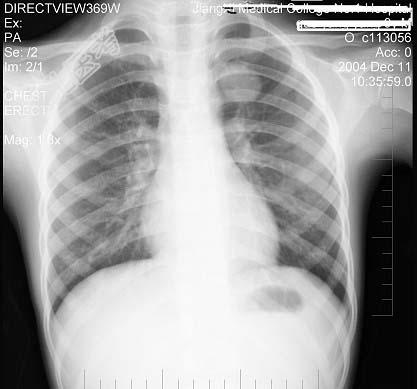

- 单项选择题男性,9岁, 常年咳嗽,无其他自觉症状, X线检查如图所示,最可能的诊断是 ( )

A、结核瘤

B、原发性肺癌

C、炎性假瘤

D、纵隔肿瘤

E、支气管扩张